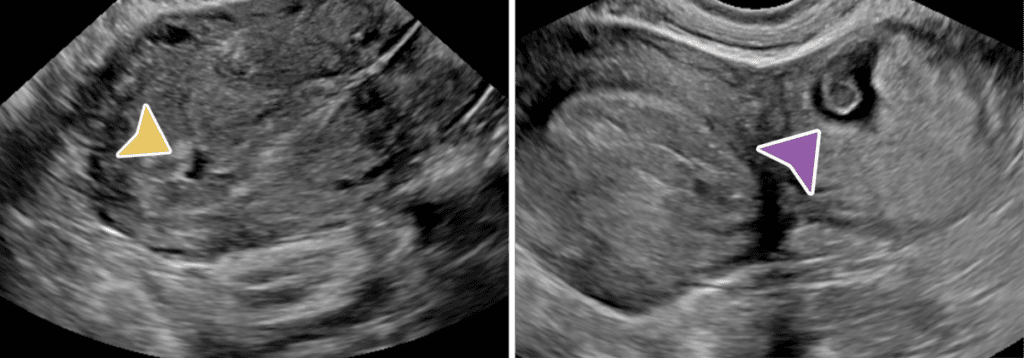

Ectopic Pregnancy: 93-97% of ectopics are tubal. Tubal ring sign has 95% PPV for ectopic. Visible double decidual sign of the intrauterine sac indicates low probability of ectopic.

Fluid in the endo canal is pseudosac (yellow arrow) vs. Ectopic (purple arrow)